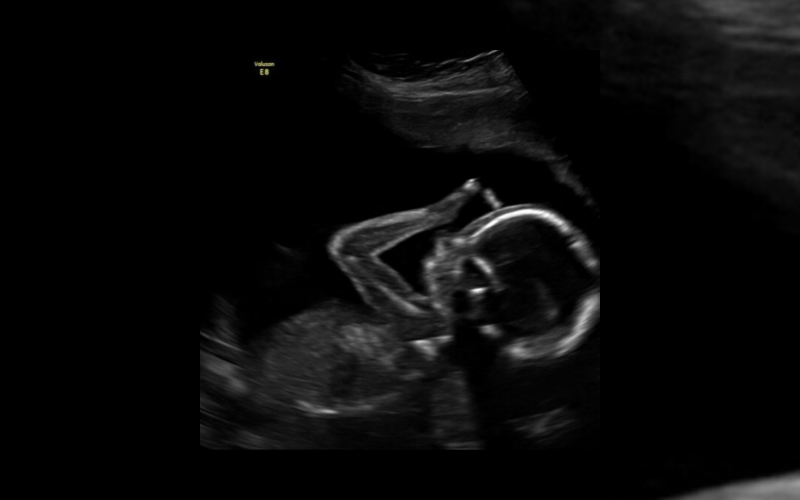

Aqui está a foto da ultrassonografia!

“Interrompemos nosso feed de santos para compartilhar esta bela imagem da vida. Nossa doce menina, com 19 semanas no útero, já está fazendo o sinal da cruz 😉✝️💕🎀 A vida é tão preciosa!

A bebê apareceu com os dedos na frente da testa, com uma postura parecida de quando começamos a fazer o sinal da cruz.

Pode ser uma coincidência, mas com certeza é algo emocionante.